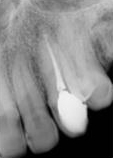

antes depois